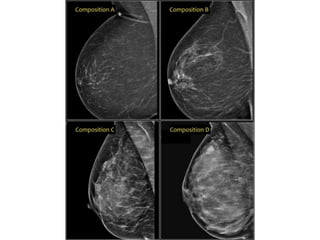

Breast imaging

• BI-RADS® is designed to standardize breast

imaging reporting and to reduce confusion in

breast imaging interpretations.

It also facilitates outcome monitoring and quality

assessment.

• It contains a lexicon for standardized terminology

(descriptors) for mammography, breast US and

MRI, as well as chapters on Report Organization

and Guidance Chapters for use in daily practice.

• A complete set of location descriptors consists of:

• Designation of right or left breast

• Quadrant and clockface notation (preferably

both)

• On US quarter and clockface notation should be

supplemented on the image by means of

bodymark and transducer position.

• Depth: anterior, middle or posterior third

(Mammography only)

• Distance from nipple

Breast imaging • BI-RADS®is designed to standardize breast imaging reporting and to reduce confusion in breast imaging interpretations. It also facilitates outcome monitoring and quality assessment. • It contains a lexicon for standardized terminology (descriptors) for mammography, breast US and MRI, as well as chapters on Report Organization and Guidance Chapters for use in daily practice.

• A completeset of location descriptors consists of: • Designation of right or left breast • Quadrant and clockface notation (preferably both) • On US quarter and clockface notation should be supplemented on the image by means of bodymark and transducer position. • Depth: anterior, middle or posterior third (Mammography only) • Distance from nipple

Mammography – breastimaging lexicon